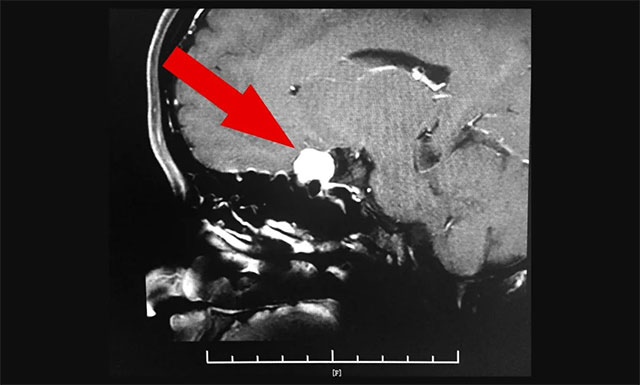

随后,完善其各项检查,为了进一步确定患者脑膜瘤位置和大小,进行了鞍区MRI平扫+增强,其左侧鞍旁可见团状肿块影,T1WI呈等信号,T2WI呈等信号,部分低信号,边缘清晰,大小约为1.5厘米x1.4厘米x1.5厘米,增强后病灶显著,均匀强化,与同侧海绵窦部分贴附。

▲ 脑膜瘤已压迫患者左侧视神经,需及时手术治疗